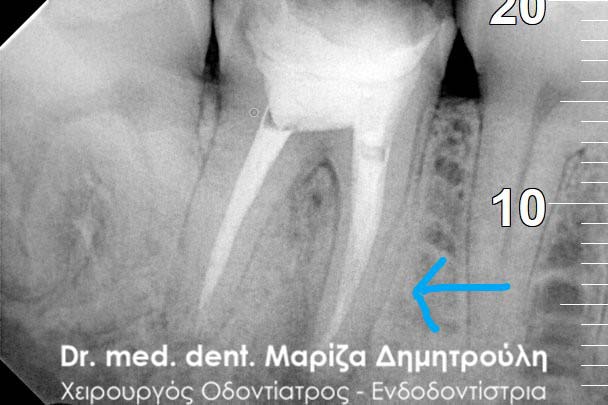

Περιστατικό – Επανάληψη απονεύρωσης δοντιού

Ο ασθενής παραπονείται για έναν μόνιμο πόνο στην περιοχή του αριστερού ιγμορείου. Ανέφερε οτι πριν χρόνια πραγματοποιήθηκε στον αριστερό γομφίο (τραπεζίτη) μία απονεύρωση. Μετά από καιρό εμφανίστηκαν τα συμπτώματα πόνου, χωρίς καμία βελτίωση. Μετά τον αποκλεισμό της ανάμειξης του ιγμορείου στη εμφάνιση των συμπτωμάτων ακολούθησε η κλινική και ακτινογραφική εξέταση του δοντιού. Η ακτινογραφία αποκάλυψε την ατελή απονεύρωση του δοντιού.

Μετά από συνεννόηση με τον ασθενή αποφασίστηκε η επανάληψη της ενδοδοντικής θεραπείας (απονεύρωσης). Ακολούθως έγινε τοποθέτηση του ελαστικού απομονωτήρα, η διάνοιξη του δοντιού και η αφαίρεση του παλιού εμφρακτικού υλικού από τις ρίζες.Επιπρόσθετα εντοπίστηκε και παρασκευάστηκε και 4ος ριζικός σωλήνας, ο οποίος δεν είχε επεξεργστεί στην πρώτη ενδοδοντική θεραπεία ( απονεύρωση ) του ασθενούς.

Διαπιστώθηκε η ενσβεστίωση 2 ριζικών σωλήνων του δοντιού (ριζών), κάτι που δεν επέτρεψε την επεξεργασία του δοντιού σε όλο το μήκος αυτών των ριζών. Παρολ΄ αυτά μετά τη δεύτερη συνεδρία ο ασθενής ανέφερε την ανακούφιση και την εξάλειψη των συμπτωμάτων, που τον ταλαιπωρούσαν τα τελευταία χρόνια.

Εφόσον το δόντι ήταν ασυμπτωματικό και ο ασθενής δεν αισθανόταν πλέον πόνο ολοκληρώθηκε η διαδικασία της απονεύρωσης με τη χρήση των μηχανοκίνητων εργαλείων και την τελική έμφραξη των ριζών του δοντιού με νέο εμφρακτικό υλικό.

ΠΡΙΝ

ΜΕΤΑ